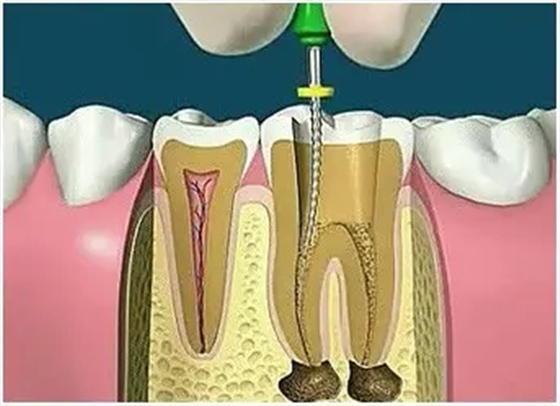

4、根管預(yù)備

根管清理成形的目的是去凈根管壁上的感染物,通過根管器械的切削作用去除感染的牙本質(zhì)并清理根管壁細(xì)菌以利于根管充填。